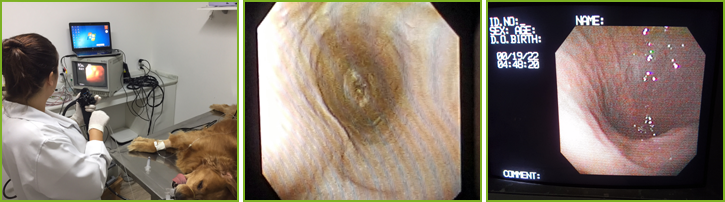

A endoscopia é uma técnica de recente aplicação na medicina veterinária, que permite visualização direta do órgão analisado, de forma não invasiva e segura. É utilizada como método diagnóstico e até mesmo terapêutico de diversas enfermidades que acometem cães e gatos.

É também, o meio mais confiável de avaliação e de obtenção de amostras de tecidos (biópsias) sem necessidade de recorrer à cirurgia. Este exame, em sua maioria, é feita para visualização de trato gastrointestinal (esôfago, estômago, duodeno, cólon e reto).

A endoscopia é a técnica de imagem que mais complementa outros métodos, e que está especialmente indicada diante de certos sintomas como: vômito, diarréia, sangue nas fezes, ingestão de corpos estranhos (bolinhas, brinquedos, pedaços de madeira e etc.), emagrecimento, falta de apetite, salivação intensa, dor abdominal, tosse, secreção nasal, dentre outros.

Para que o exame seja realizado é necessário que o animal seja submetido à anestesia geral, por isso a indicação do procedimento pode ser feita somente após uma cuidadosa avaliação do clínico veterinário.